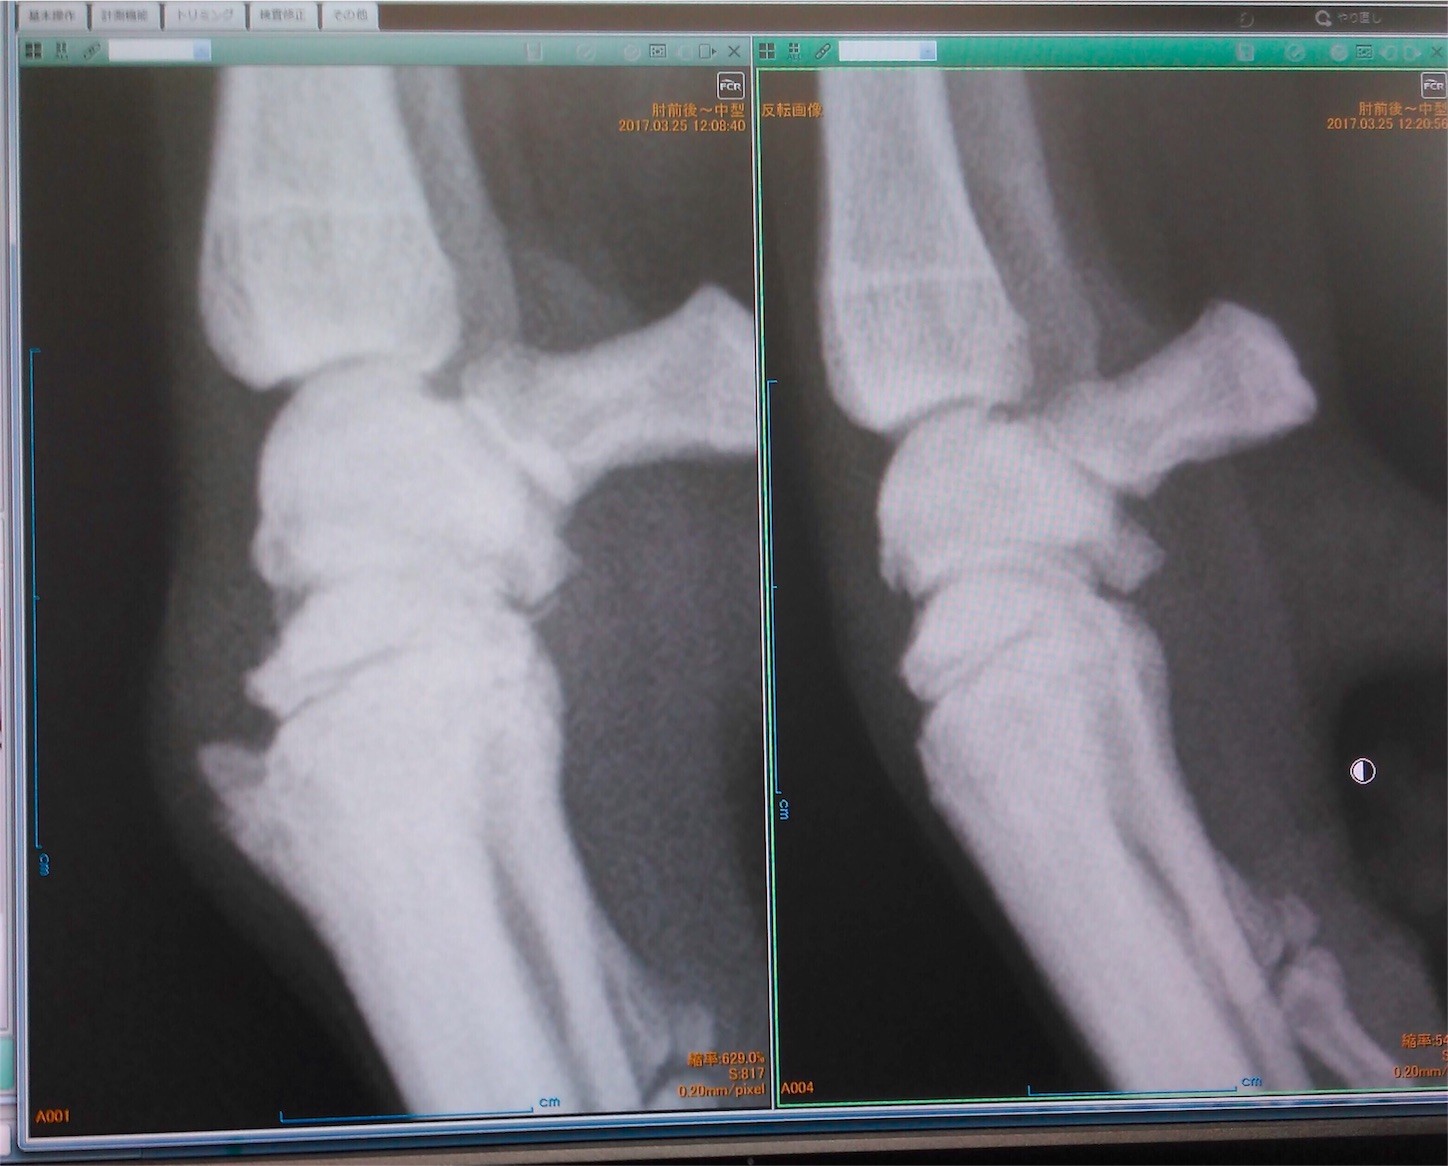

レントゲンを撮ってみると、骨が変形していた

右前脚 左前脚

診断としては関節炎で、ウィペットは走るのに脚に負担がかかるので

年齢を重ねると共にある程度は仕方ないとのこと。

ちなみに細かく言えば左の方も軽く関節炎になっているそうな。

勿論、骨が元に戻ることはない。あと、ヘルニアでも無いらしい。